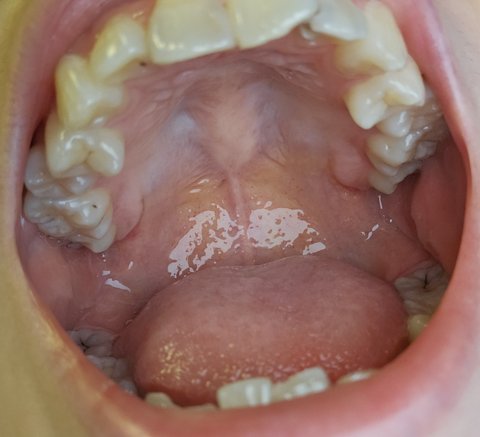

내 이빨 좀 제발 도와주셈

제가 어렸을때부터 조금 빈곤하게 자라왔고 가정환경이 안 좋았다보니 양치질도 잘못배워서 초~중학생때부터 양쪽 상하 어금니에 충치가 자리잡아있었는데요.

고등학교 때부터 올바른 양치질을 터득하고 열심히 관리했지만 충치+치석+ 이빨 깨짐이 이미 생겨버려서...

현재 제 나이 22살, 빨리 직장 생활 시작하고 이제 돈도 제가 어느정도 벌어서 치료를 시작하려고 하는데 정말 너무 막막하고 눈물만 나와요... 마음같아선 다 발치갈기고 임플란트 심어버리고 싶을 정도로 막막해요.

(+앞니는 벌써 이렇게 깨졌어요...언제 반토막 날지도 모르겠는데 치과 알아보느라 아직도 방치중이에요...)